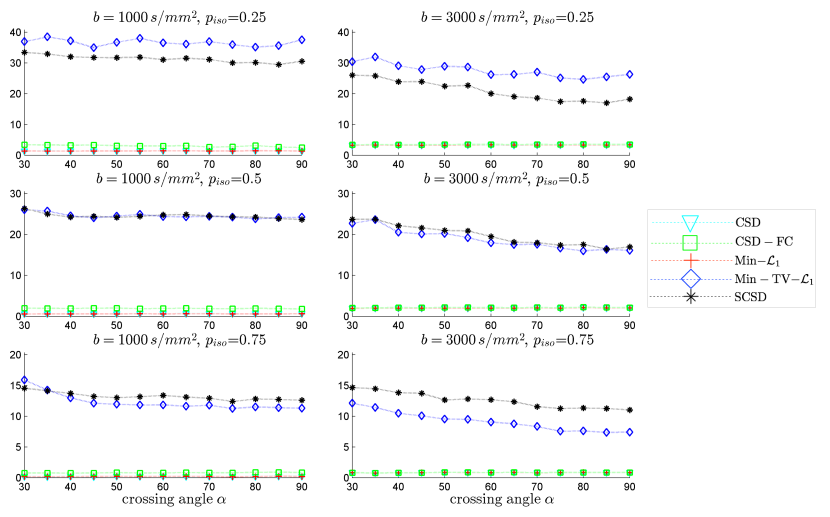

The results of our final quantitative comparison are summarized in Fig. 7, which shows the values of contrast obtained using different SD methods under comparison for s/mm2 (left column of subplots) and s/mm2 (right column of subplots). Predictably enough, the best contrast is achieved by the Min-TV- and SCSD algorithms, owing to their inherent ability to account for the presence of isotropic diffusion. Moreover, out of the two, the proposed SCSD algorithm yields the higher values of for all simulated scenarios. An additional illustration of the effect of incorporation and spatial regularization of the isotropic diffusion component is provided in Fig. 8, which depicts a 2-D “axial” slice of the IDMs reconstructed by different SD methods under comparison for s/mm2, , and . (Note that, for the sake of the clarity of visualization, the IDMs in Fig. 8 have been normalized so as to make their minimum and maximum values correspond to black and white pixel values, respectively.) One can see that the IDM reconstruction produced by SCSD is virtually indistinguishable from the original IDM (as shown in the upper, leftmost subplot of the figure), with the second best result produced by the Min-TV- algorithm. At the same time, neither CSD, Min- nor CSD-FC can attain a comparable accuracy of estimation of the spatial pattern of isotropic diffusion, as represented by the original IDM. In particular, even though their respective reconstructions do bear some global resemblance to the original IDM, the level of estimation errors is too high to deem these reconstructions useful.